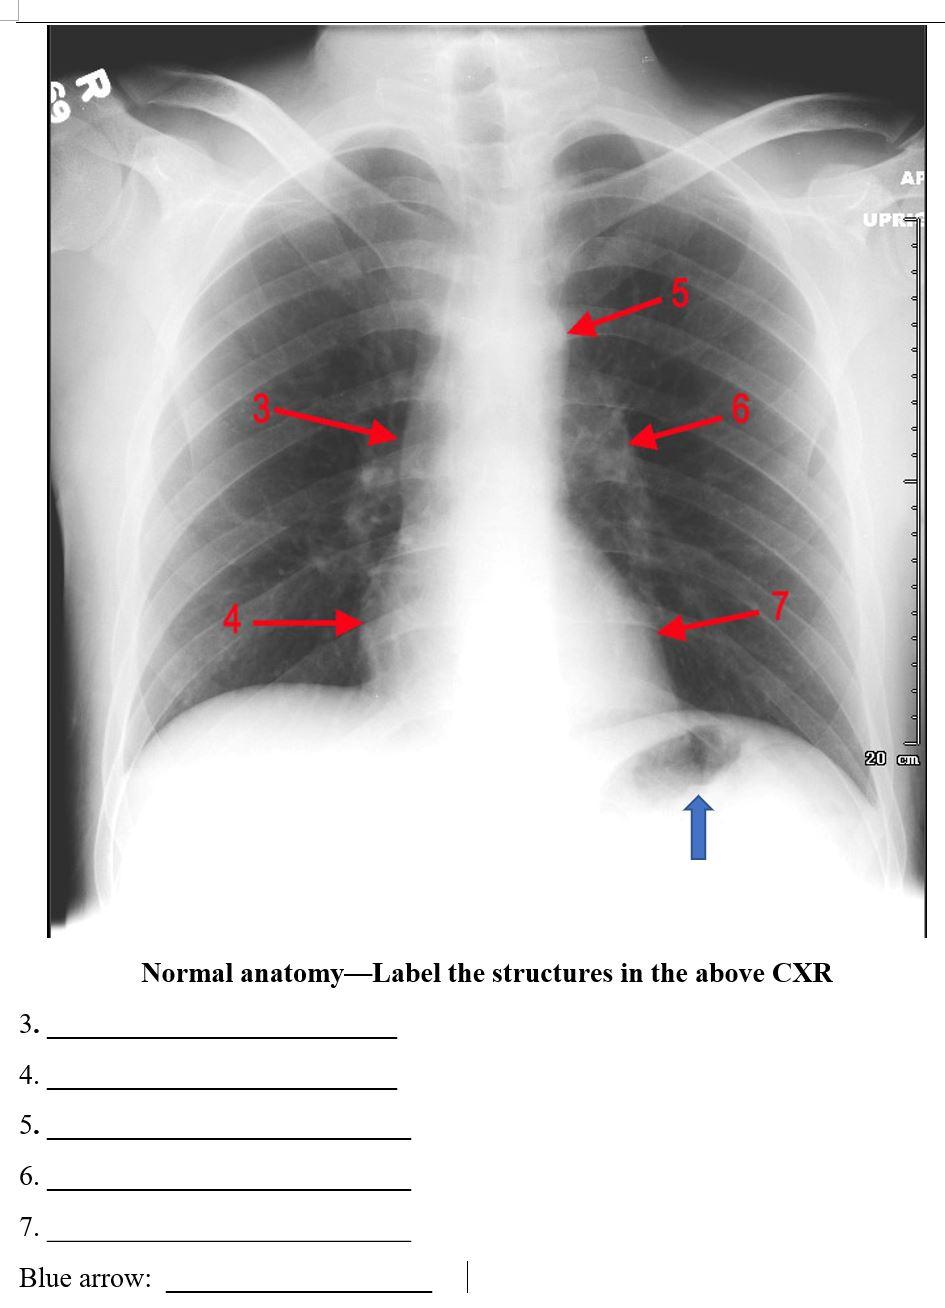

45 label the structures in the chest x-ray using the hints provided.

Label the structures in the chest x-ray using the hints provided.

Label the structures in the chest x-ray using the hints provided.. Solved Thorax X-ray 79 Label the structures in the chest | Chegg.com Thorax X-ray 79 Label the structures in the chest x-ray using the hints provided points Aortic knob doc Apex of heart mos Superior vena CAVA Right bordet of heart Lott border of heart AHCDW14Notes18.pdf - 18. Award: 10.00 points Problems?... visible and typically consists of three to five lobes connected by slender nuclear strands. The two remaining WBC types—monocytes and lymphocytes—are called agranulocytes because they lack specific granules. Monocytes are two or three times the diameter of an RBC. AHCDW15Notes32.pdf - 32. Award: 1.00 point Problems? Adjust... Drag each label to the appropriate position to identify whether the structure contains oxygenated or deoxygenated blood. Explanation: Arteries carry blood away from the heart. Veins carry blood toward the heart. With the exception of the pulmonary circuit and the Frontal Radiograph | SpringerLink Understanding the basic components of a frontal view chest radiograph and its limitations is the cornerstone for mastering its literacy in order to successfully overcome those instances when the radiographs can challenge your confidence to diagnose. Keywords Frontal Heart borders Lung lobes Pleura AP PA Hilum Download chapter PDF Further Reading

Solved Thorax X-ray -6 Label the structures in the chest | Chegg.com Best Answer 1) AORTIC KNOB 2) SUPERIOR VENA CAVA 3) RIGHT B … View the full answer Transcribed image text: Thorax X-ray -6 Label the structures in the chest X-ray using the hints provided Superior vena cava Aortic knob rences Apex of heart Right border of heart Loft border of heart Aorticoob Apex of heart Name the structure Reset Zoom